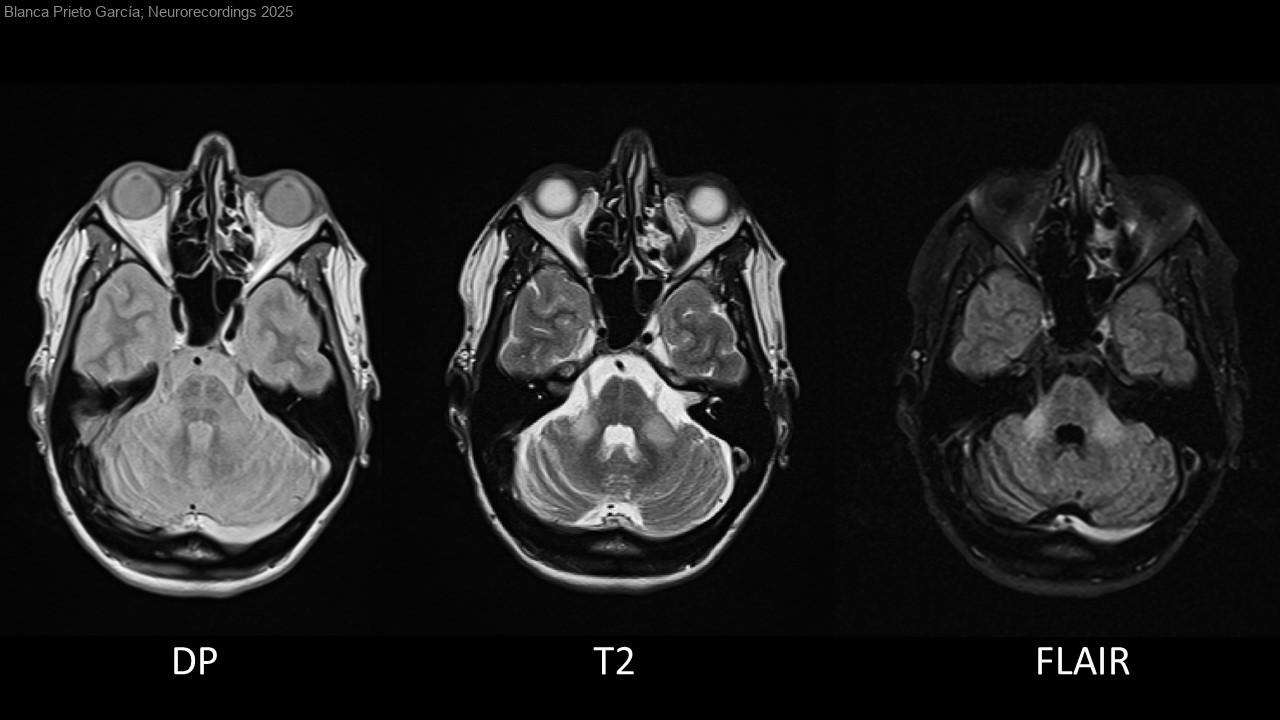

Atrofia multisistémica: trastorno de la marcha y signo de la cruz

Diagnóstico final: Atrofia multisistémica subtipo cerebeloso

Mujer de 45 años con antecedentes de migraña y trastorno ansioso-depresivo. Refiere mareos, vértigos, inestabilidad a la marcha y alteración en la articulación del habla desde hace 3 meses. A la exploración se evidencia disartria...